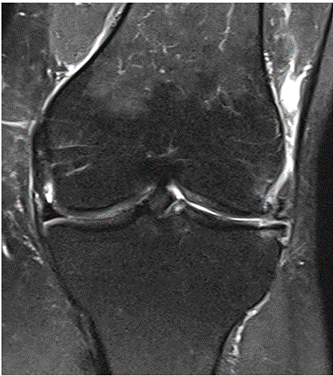

MRI scans illustrating the improvements regarding Group 2 are presented below, showing pre-treatment images with evident cartilage defects, pronounced bone marrow edema, and synovial inflammation, followed by post-treatment scans demonstrating improved joint structure, reduced edema, and decreased inflammation (Figures 12-29).

MRIs of Group 2

Figure 12: Female, 59 years, pre-intervention MRI.

Figure 13: Female of figure 12, 59 years, two-month follow-up MRI: MSC plus ChondroFiller® liquid.